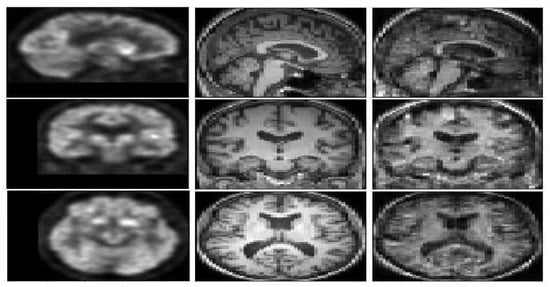

Figure 4 represents a FDG-PET sample, a ground truth MRI image, and the generated image. The generated T1 weighted MRI, visually is quite the same as the ground truth. In order to compare the result with the state of the art methods Figure 5, represents a visual comparison between the proposed model and the three methods in the state of the art.

Figure 4.

A pair of FDG-PET (left image), the ground truth T1 weighted MRI (middle image), and the generated image (right image) with E-GAN.

Figure 5.

Experimental results for translating PET images to corresponding MRI with 3D DCGAN [35], 3D WGAN [25], 3D Pix2Pix GAN [17], and the proposed method.

According to Figure 5, WGAN and DCGAN are defeated by Pix2Pix GAN and the proposed model in terms of visual assessment. The proposed method has higher quality and almost no artifacts and blurriness compared to Pix2Pix GAN.

The DCGAN almost could not generate the uniform tissues and the generated image only has the main structure of the T1 weighted MRI. While the synthetic result of the WGAN has a better performance on synthesizing the structure of T1 weighted MRI, the synthetic images often preserve noise. The Pix2Pix GAN architecture obtains more details inside the tissues but both the Pix2Pix GAN and the WGAN performed poorly for the boundaries and sometimes visual artifacts in the corner of the synthetic images. E-GAN shows a good performance in terms of generating boundaries and edges.